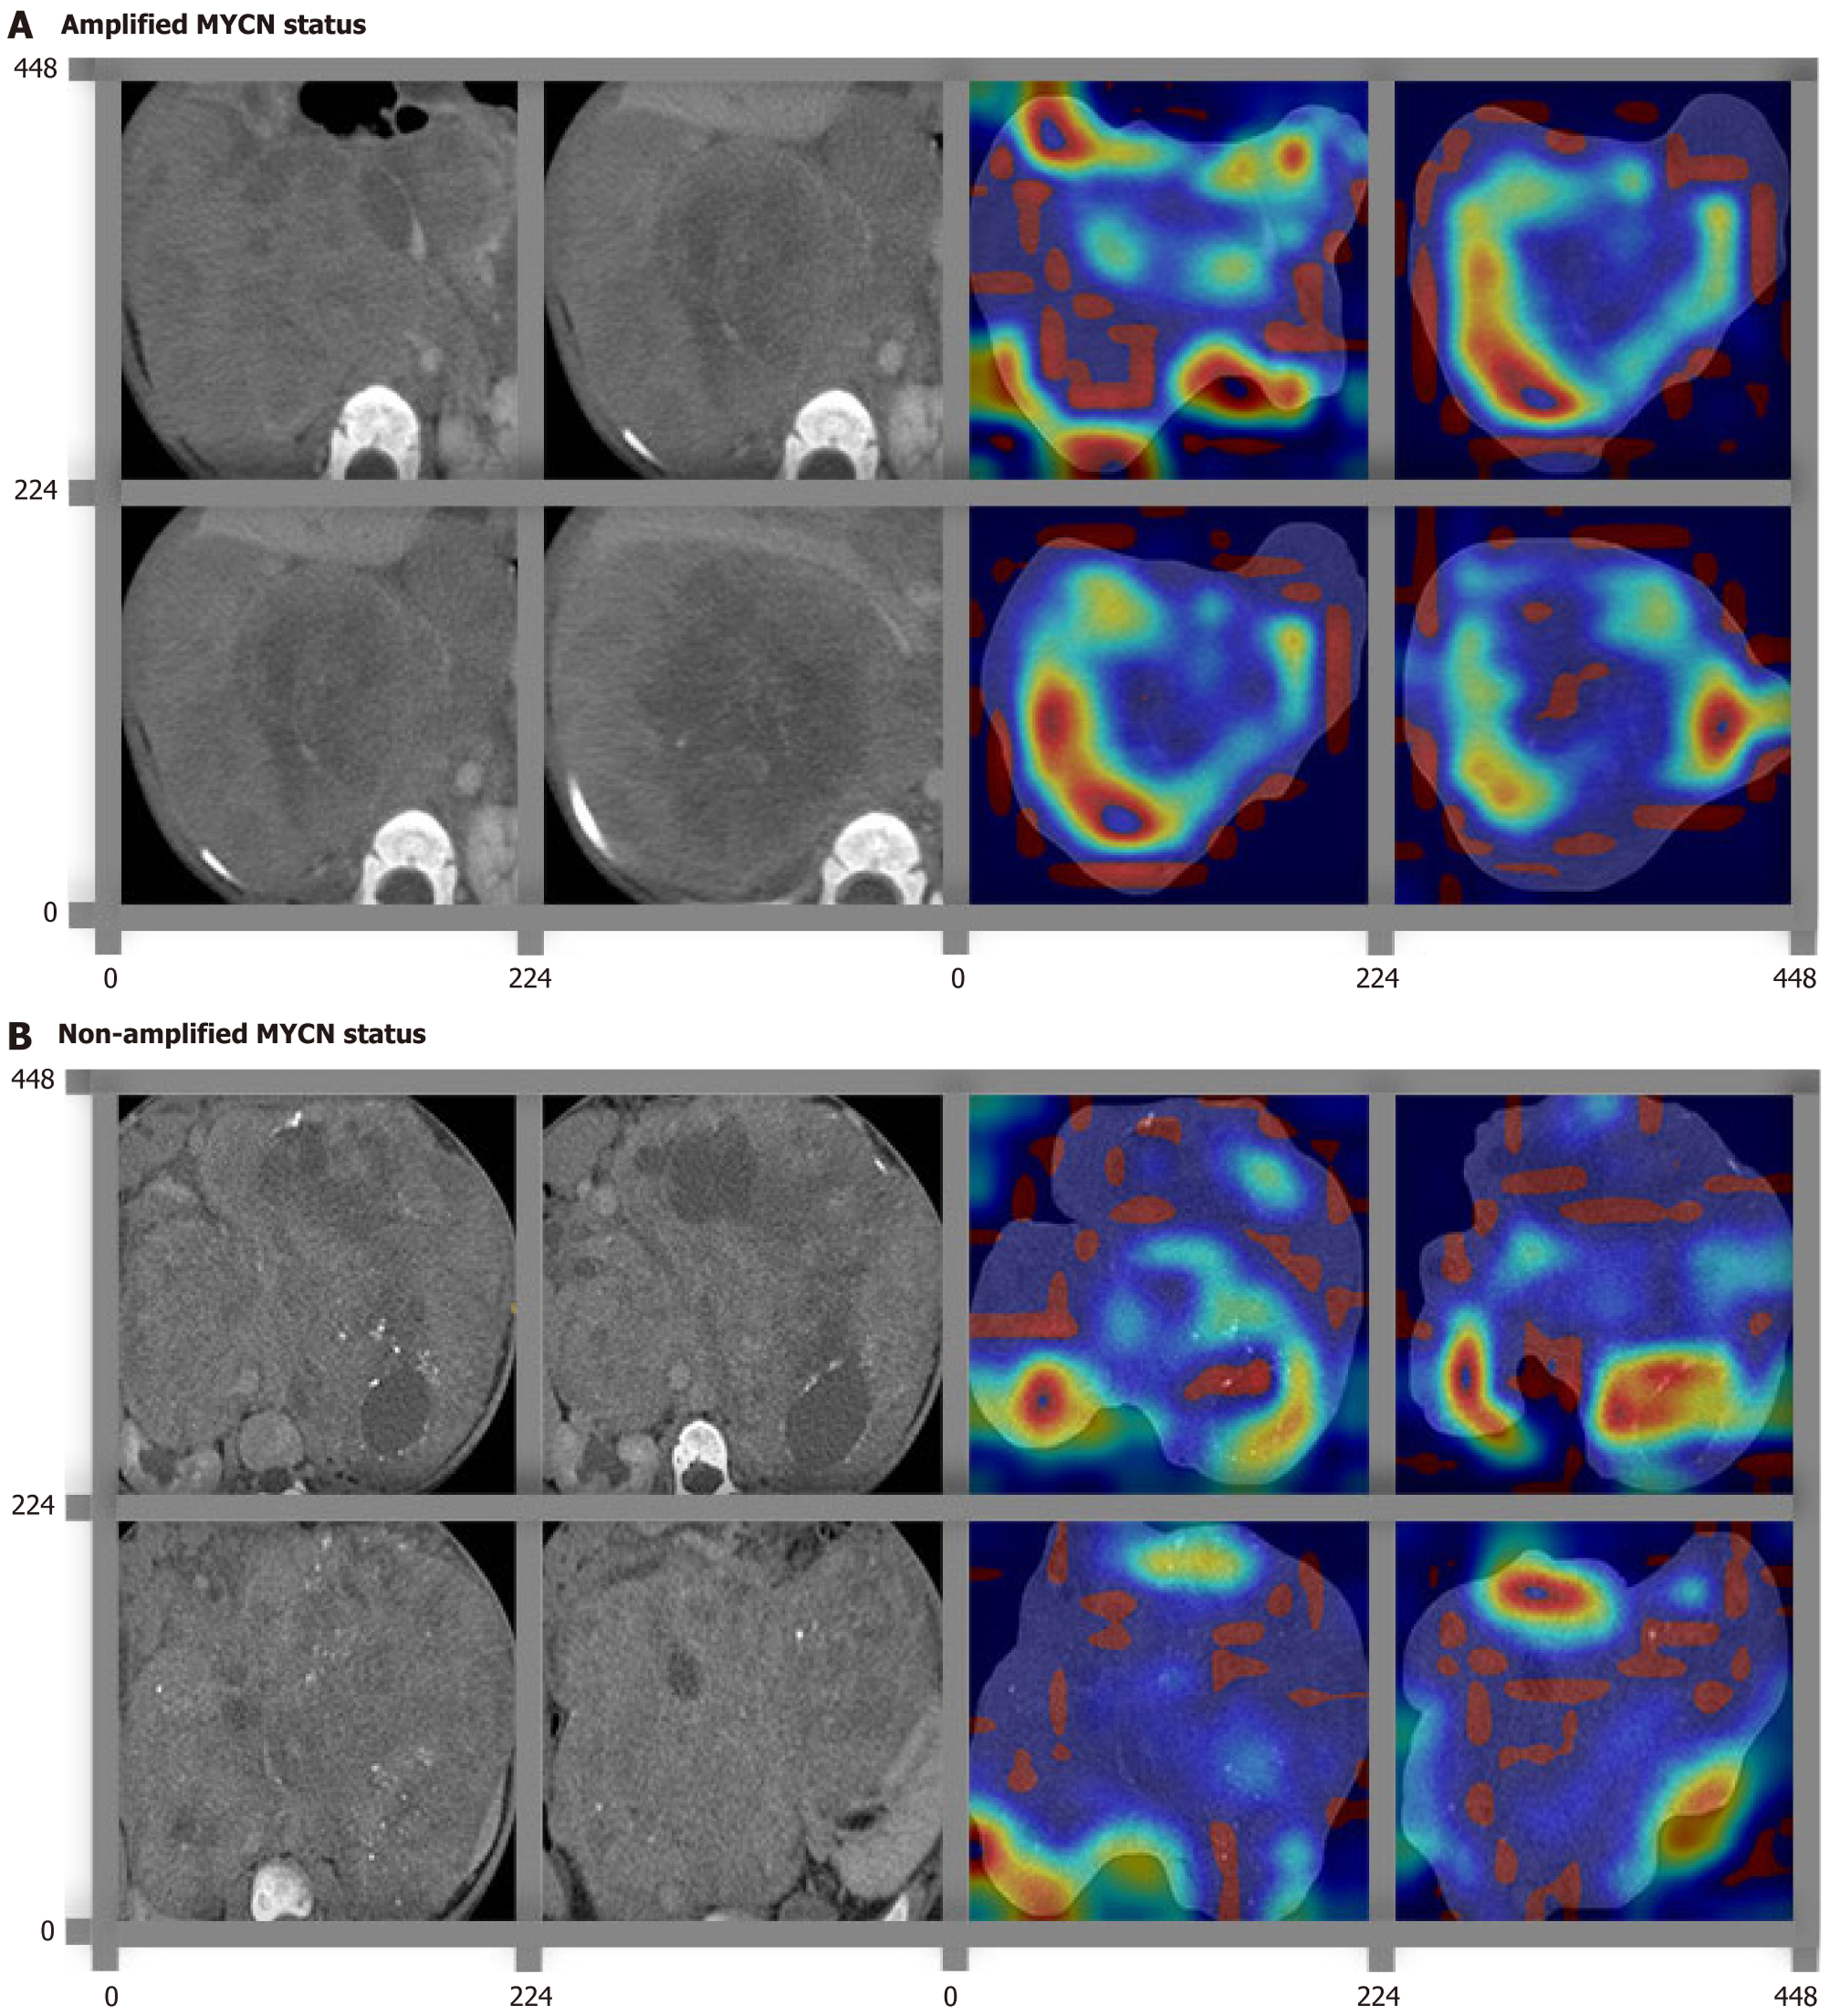

Figure 2 Feature heatmaps of representative histological patterns in bladder cancer on the deep learning ResNet50 algorithm via the Guided Grad-Class activation mapping.

A and B: The original computed tomography images and their corresponding feature heatmaps were shown in left and right sides, respectively. The red color highlighted the region of interest to classify MYCN amplification. Different subregions were recognized and highlighted in different MYCN statuses, including amplified MYCN status (A) and non-amplified MYCN status (B).